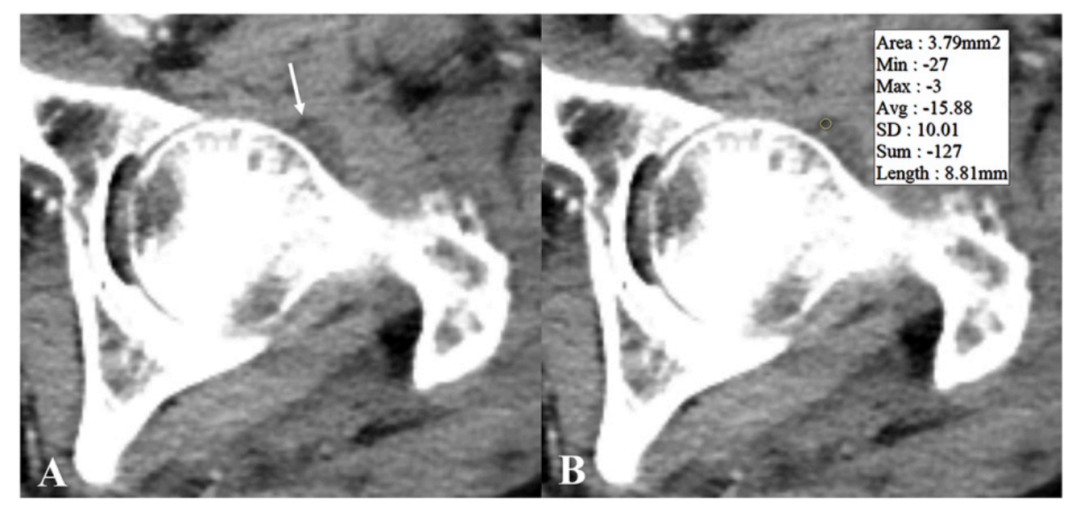

图1 CT软组织窗可见由关节积脂血症导致的囊性征(箭头所示)。测量图B黄色圈内CT值平均为-17。

CT表现:CT可以清楚地显示关节腔内的脂肪和血液及两者形成的液-液平面,有时还可以出现3层,即上层为脂肪,中层为关节液,下层为血液。关节囊内的脂肪CT值约为-130~-100 HU,而关节囊内的血液CT值约为10~30 HU。有时出血和关节腔积液分辨不清,常被笼统地认为关节腔积液。